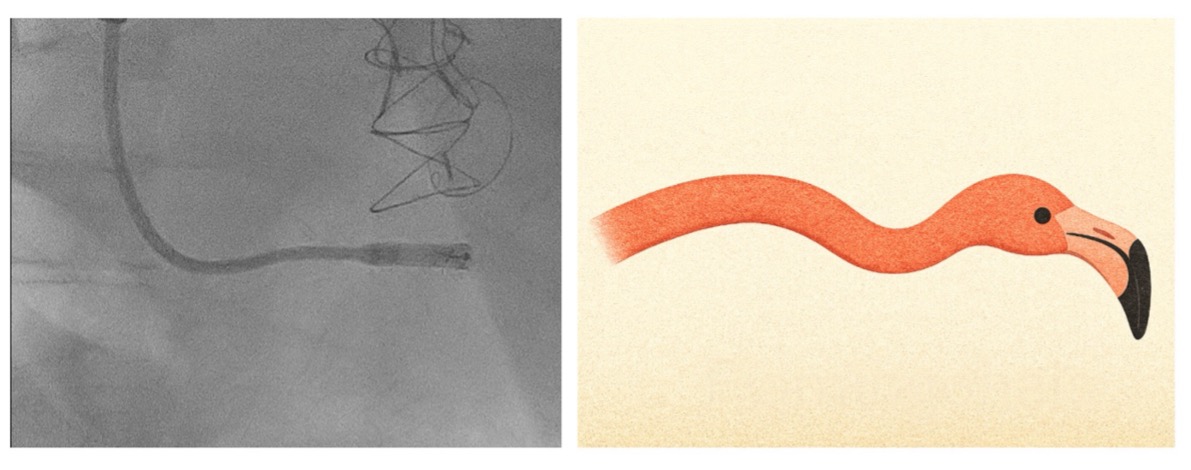

The transjugular route provided superior catheter control and facilitated septal positioning within the markedly dilated right heart. Correct septal contact was verified by the fluoroscopic “flamingo-neck” configuration (Figure 2) and contrast injection. Despite multiple repositioning attempts, implantation was successfully completed without complications. Pacing thresholds were stable, and the patient was discharged two days later in good clinical condition. A subsequent methicillin-sensitive Staphylococcus aureus bacteremia was unrelated to the device.

Figure 2: lef: Fluoroscopic image: leadless pacemaker delivery catheter in the right ventricle; right: schematic illustration of “flamingo-neck” configuration during septal positioning (generated by OpenAI, 2025)